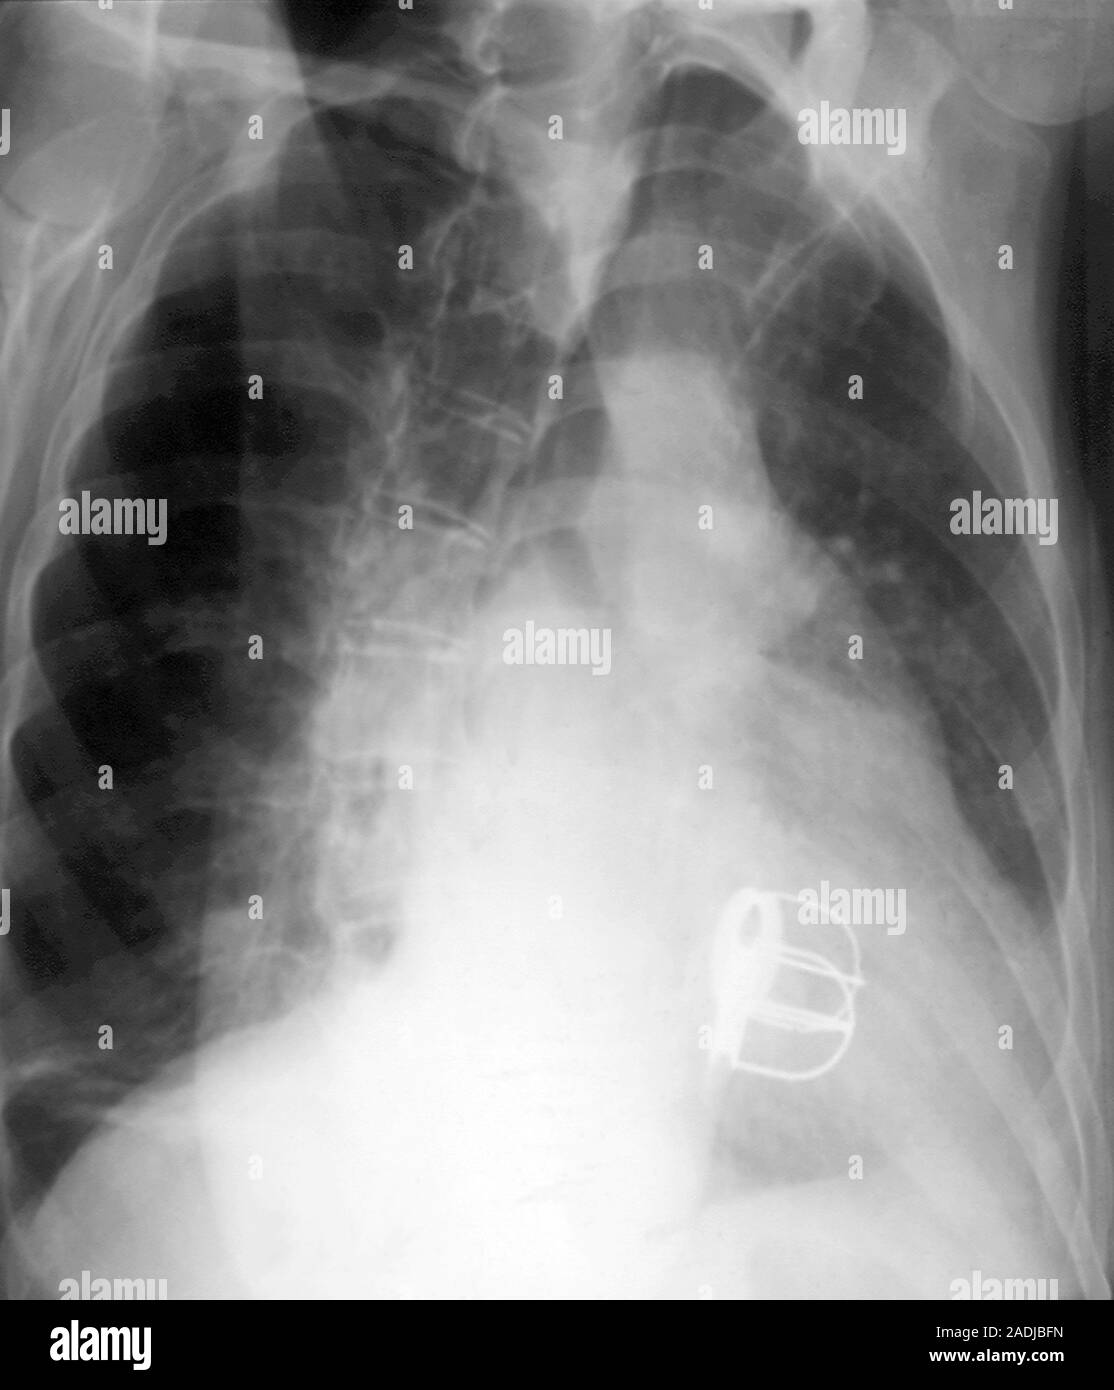

Prosthetic heart valves. Xray, taken diagonally from the right, of a Can A Person Live With An Artificial Heart It helps restore circulation and controls the flow of blood to and from the heart. (bivacor) it took ten years, multiple designs, and dozens of animal studies, but the. bivacor total artificial heart. a total artificial heart (tah) is a device that replaces the heart’s damaged ventricles and valves. an investigational 50cc pump currently in clinical trials. Can A Person Live With An Artificial Heart.